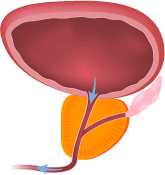

Eliminar eficazmente los síntomas y las causas de la prostatitis

(ayuda a aliviar la inflamación, eliminar el estancamiento en la pelvis, disminuye el tamaño de la próstata)